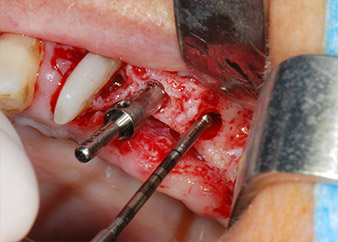

Prior to implant placement, infected tissue was removed from the alveolar bone in the implant site and around the abutment teeth with an insert originally designed for bone shaping and collecting bone chips (Piezomed, insert B5) (Figs. 6 and 7).

IImplant beds were prepared at sites 25 and 26 with rotary instruments, used in a contra-angle handpiece with a 20 : 1 transmission ratio with an updated powerful implant motor (Implantmed, W&H) (Fig. 8).

The final preparation next to the sinus was again carried out with a piezoelectric instrument (Piezomed, insert S2).